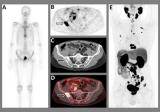

核医学!复旦大学附属肿瘤医院宋少莉/郭伟剑教授团队的最新成果

近日,复旦大学附属肿瘤医院宋少莉/郭伟剑教授团队的最新成果在核医学领域顶刊The Journal of Nuclear Medicine(中科院1区)发表题为Granzyme B PET/CT Imaging Evaluates Early Response to Immunotherapy in Gastric Cancer 的研究。研究团队利用首创研发了颗粒酶B高特异性靶向PET/CT探针,并将其命名为[68Ga]Ga-NOTA-GSI,通过前瞻性研究探究[68Ga]Ga-NOTA-GSI PET/C 2024-10-17 核医学